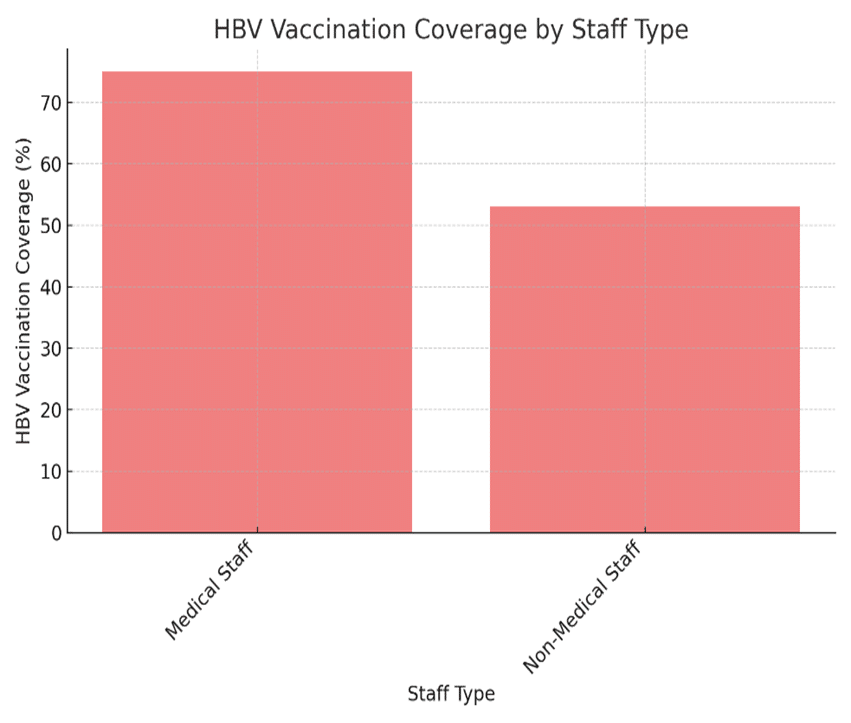

Needle-Stick Injuries and Hepatitis B Vaccination Gaps in Medical Laboratories: A Review of Risks and Institutional Responsibilities in Tertiary Institutions

In higher education institutions, individuals frequently come into contact with blood and bodily fluids, leading to infection risks. These injuries...Read More